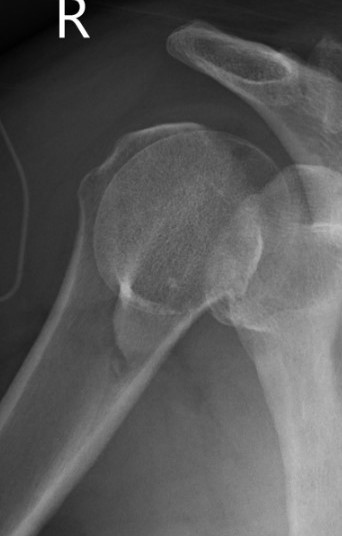

Two part

Displaced greater tuberosity fracture

Displaced lesser tuberosity fracture

Two part proximal humerus fracture

Two part proximal humerus fracture dislocation posterior